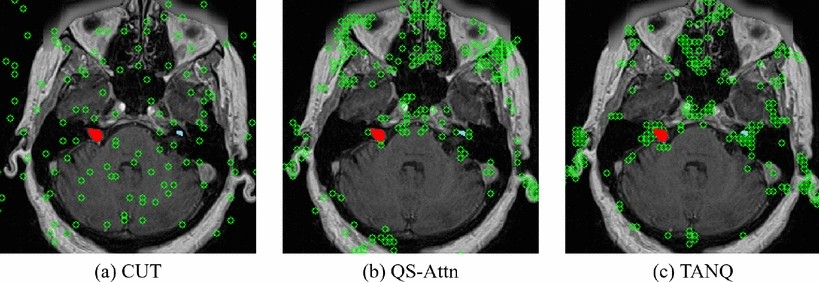

Fig. 5

Visualization of the locations(green circle) of selected features when calculating the contrastive loss. The red indicates VS, and sky-blue represents cochlea in the \(\text {ceT}_1\) image.